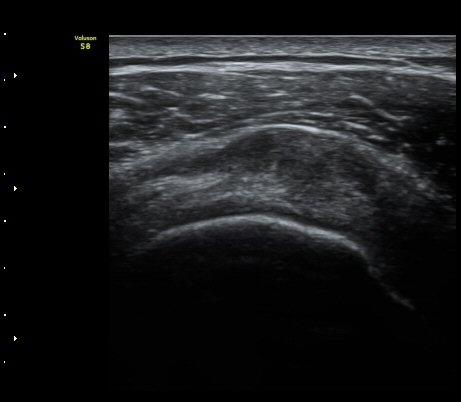

±Ø»ó°Ç³»Ãø Á¾´Ü¸é°Ë»ç¿¡¼­ ±Ø»ê°Ç ºÎÂøºÎÀÇ  ÀÛÀº ÆÄ¿­°ú Á¡¾×³¶ ºÎÁ¾ÀÌ °üÂûµÊ(±×¸² 2, 3).

±Ø»ó°Ç ¿ÜÃø Á¾´Ü¸é°Ë»ç ½Ã Á¡¾×³¶ ºÎÁ¾ÀÌ °üÂûµÊ(±×¸² 4).

±Ø»ó°Ç ±ÙÀ§ºÎ ±Ø»ó°Ç ³»ÃøÀÇ Àú¿¡ÄÚ ºÎÁ¾°ú Á¡¾×³¶ ºÎÁ¾ÀÌ °üÂûµÊ(±×¸² 5).

±Ø»ó°Ç ¿øÀ§ºÎ ±Ø»ó°Ç ºÎÂøºÎ ÀÛÀº ÆÄ¿­ÀÌ °üÂûµÊ(±×¸² 6).